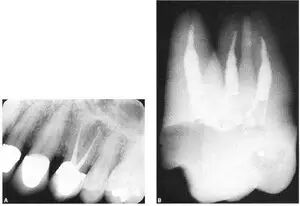

crown-down技术要求冠部髓腔预备完成后器械可以直线进入根管,高速球钻这时简直是捣乱。尤其我一直采用的是“平面开髓”见下图:

口腔H锉怎么消毒牙科医生必须看看----经典根管治疗总结_https://www.jmylbn.com_新闻资讯_第9张

图 平面开髓1

口腔H锉怎么消毒牙科医生必须看看----经典根管治疗总结_https://www.jmylbn.com_新闻资讯_第10张

图 平面开髓2

关于“平面开髓”:注意到开髓的时候不是一个“点”,而是一个平面,这个平面略小于髓腔,在髓腔的正上方,在开髓的时候是一层一层深入的,这种方法的好处:1、随时可以观察到露髓点,2、即使是增龄性变化很大的牙齿,也不会损伤到髓室底。缺点是:需要对髓腔形态烂熟于心中,要不然有时会过多破坏牙体,说到这个其实不是问题,要想做一个合格的牙体牙髓大夫,这是必要条件。那么你想想,球钻能弄好“平面开髓”吗?